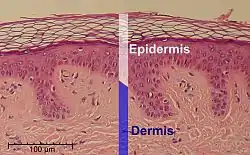

Microscopic image of the epidermis, which constitutes the outer layer of skin, shown here by the white bar | |

Epidermis and dermis of human skin

Epidermis and dermis of human skin Cross-section of all skin layers